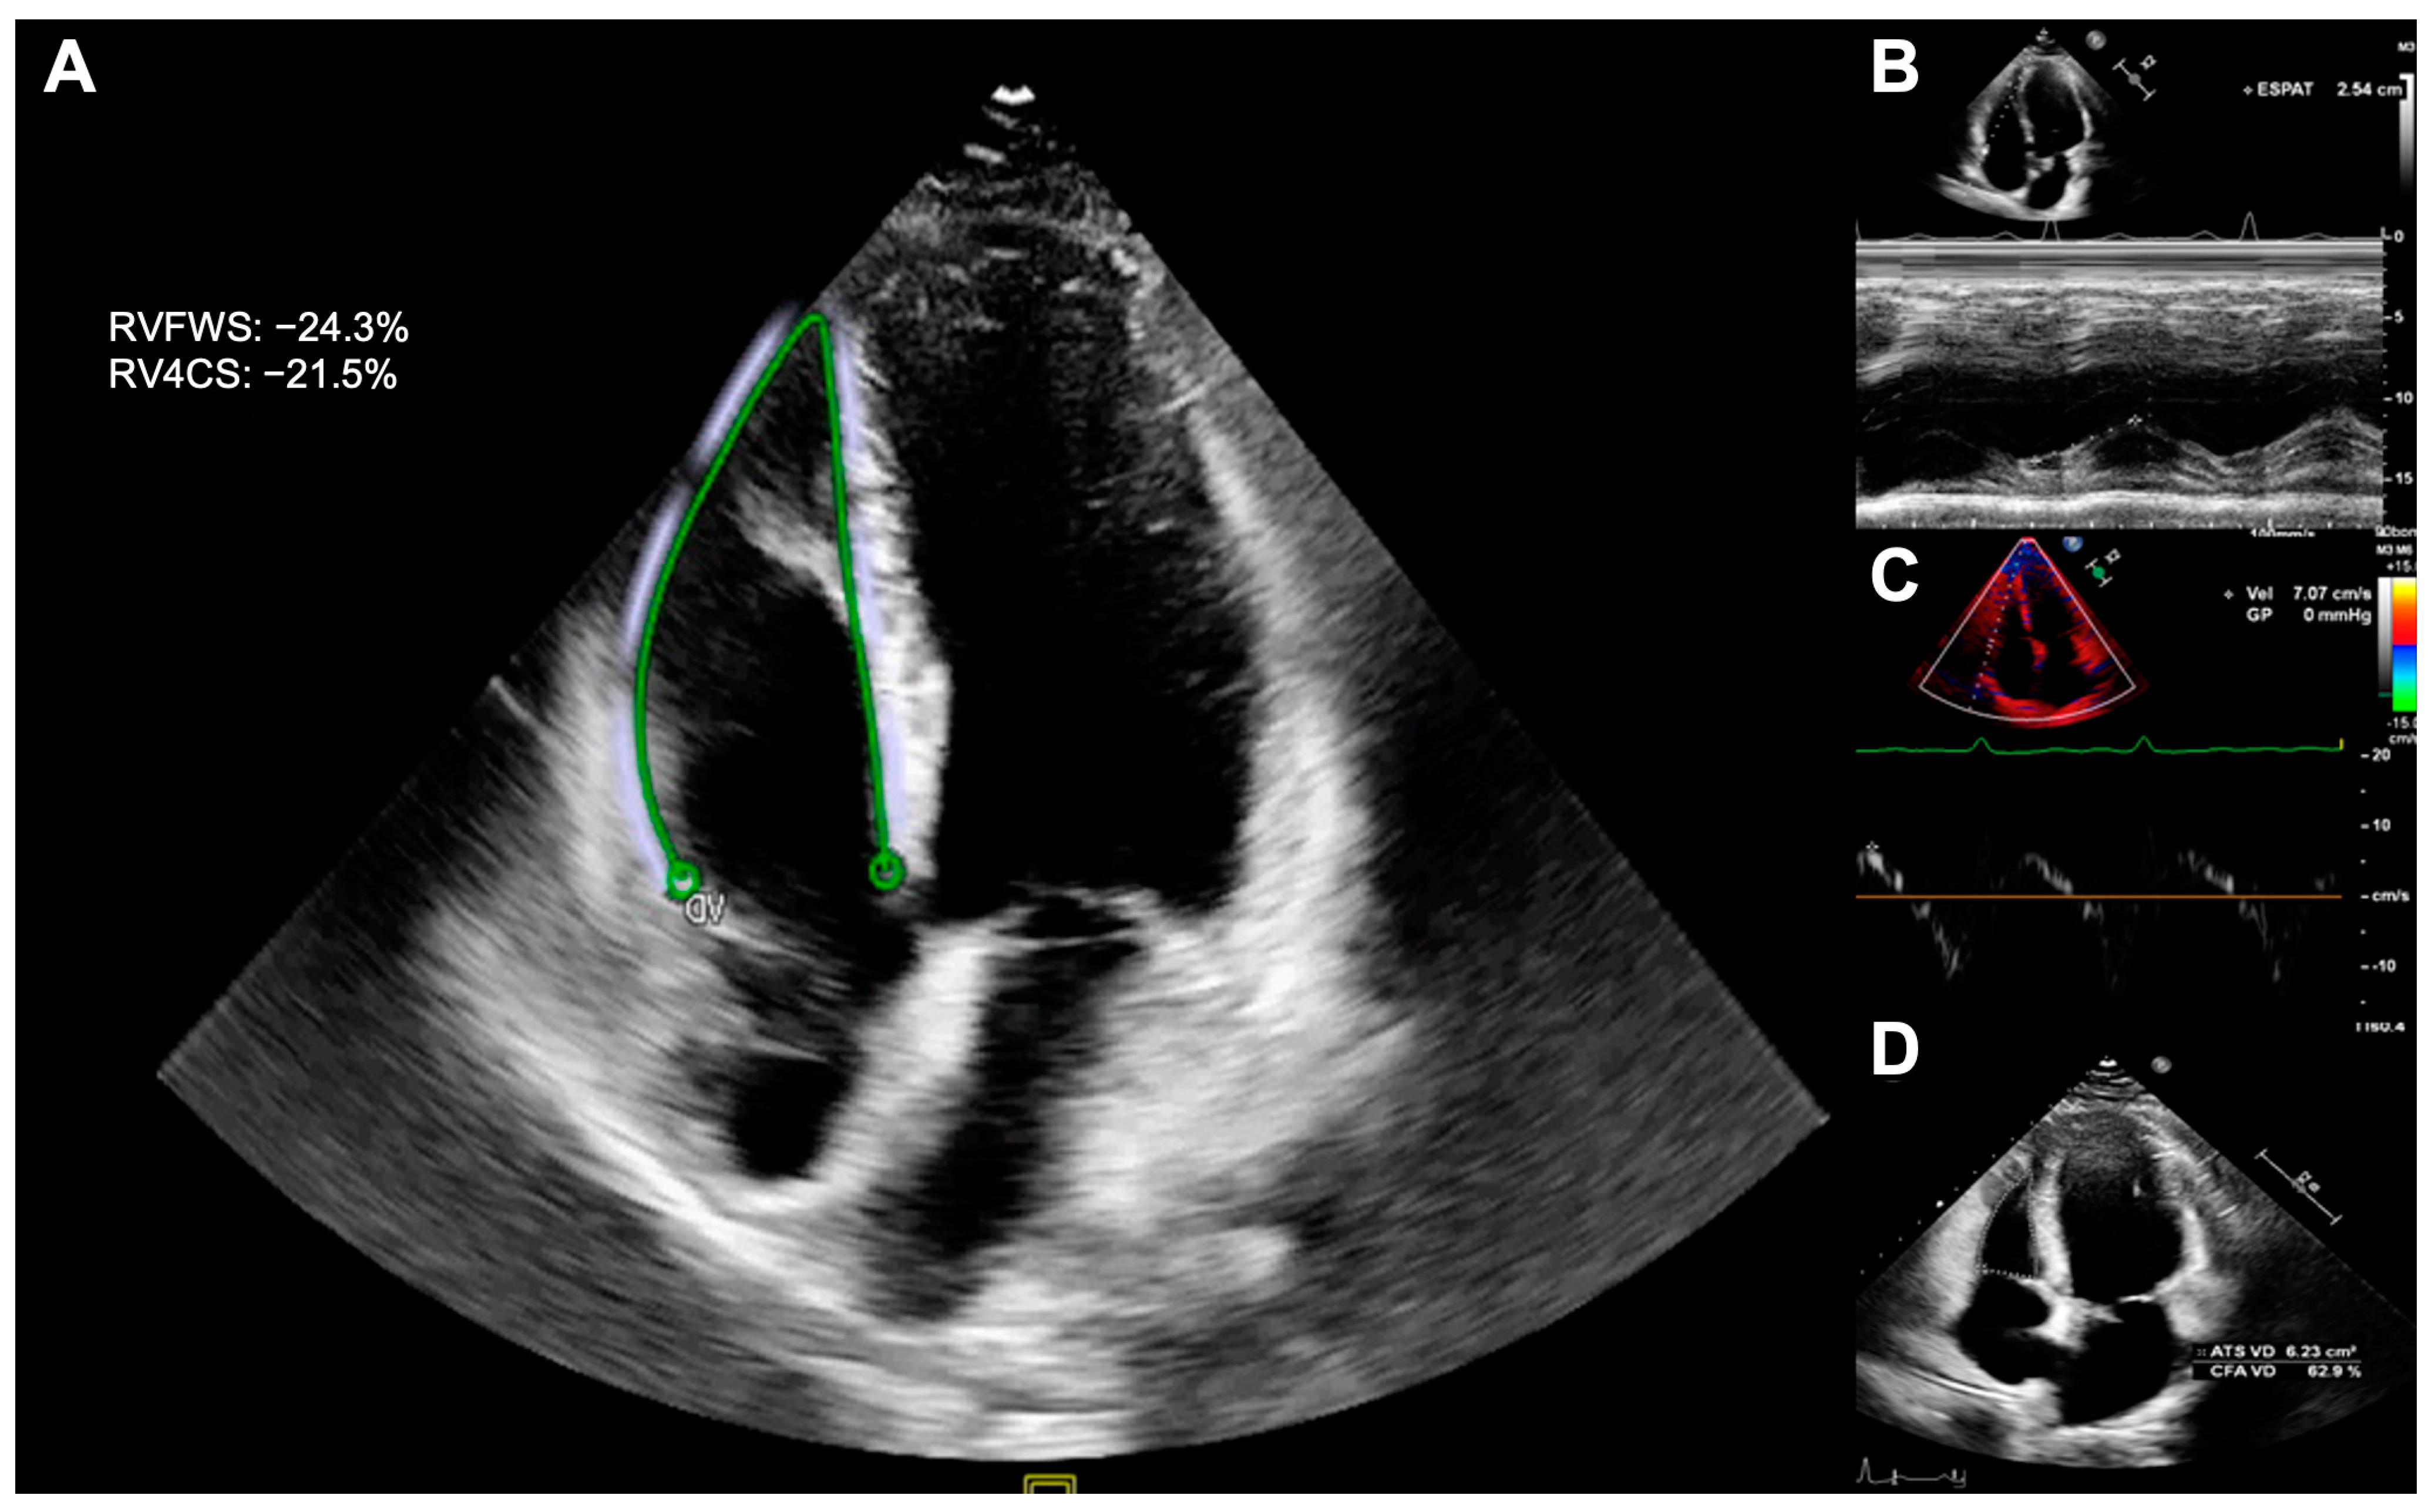

| RVFWS (-%) | 24.9 ± 4.6 | 26.8 ± 4.7 | 0.032 | 1.92 (0.85) | 0.025 |

| RV4CS (-%) | 21.7 ± 3.3 | 23.1 ± 3.4 | 0.017 | 1.57 (0.64) | 0.016 |